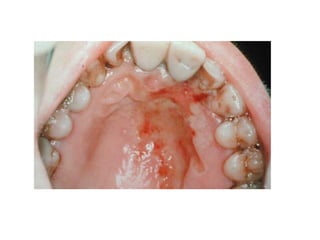

1 -1ry herpes

simplex

Onset: after 6 months ,Peak

within 2-3 years

2-generalized acute marginal

gingivitis

4-mainly keratinized gingiva

5-mainly at anterior area of

oral cavity